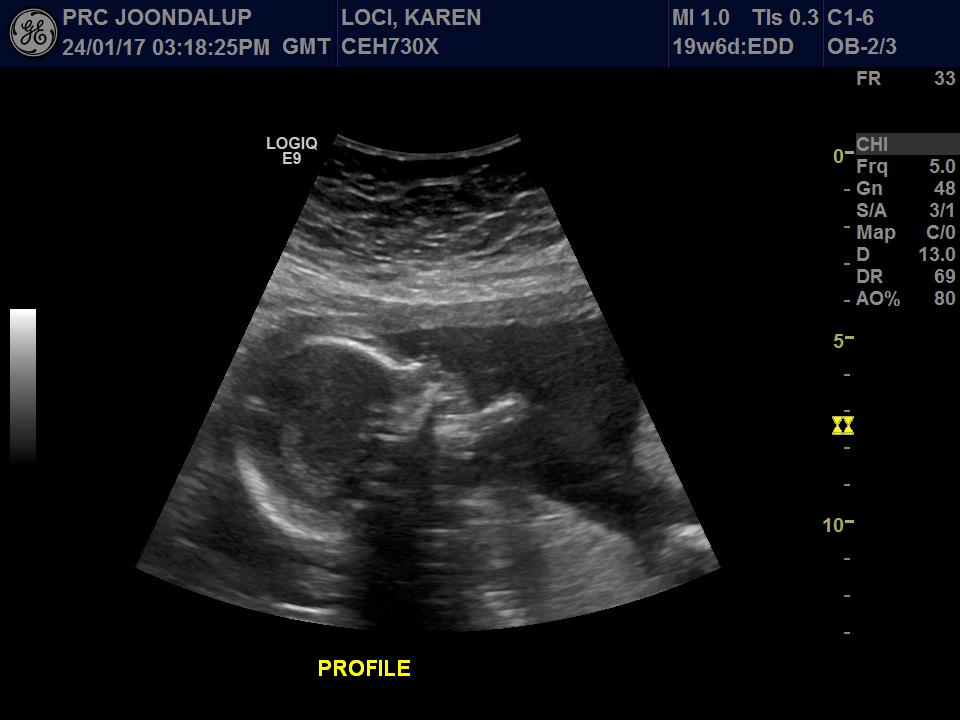

I had my 20 week scan 2 weeks ago and the tech said it looks like a boy but she also stated that girl bits can be swollen.

7th is 20 weeks